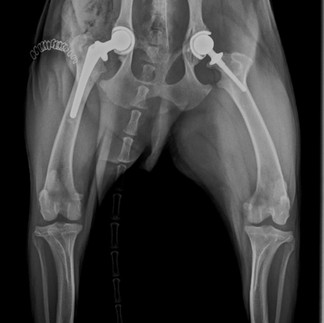

Every summer, we take x-rays of Ducky’s hips to not only evaluate the stability of his left hip implant, but also check for any further evidence of worsening arthritis due to Hip Dysplasia in his right hip. When comparing Ducky’s July 2022 x-rays to his July 2019 x-rays, not much has changed radiographically in his right hip (which is a good thing!), but Ducky has always been a bit of a special case. He never really showed severe clinical signs like his x-rays would suggest, which you can see below.